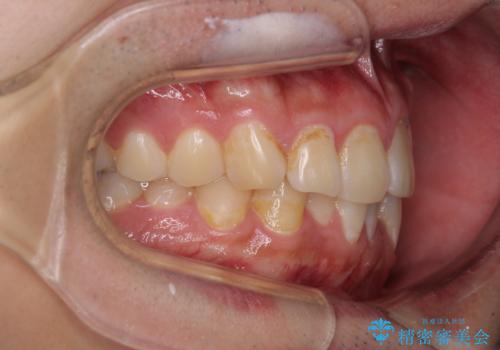

写真より左側臼歯の咬合がタイトではないことが分かりますが、こちらは保定期間に徐々に咬合させていくこととしました。